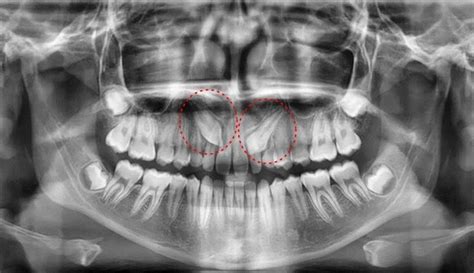

El diagnóstico es más habitual de lo que se piensa: dientes impactados y transpuestos, que es de lo que vamos a hablar en este artículo. Los dientes impactados son los que están todavía dentro del hueso y han perdido el camino natural de salida dentro de la boca. Pueden estar cruzados en su posición o incluso hacia el centro del paladar, así pueden salir en otras partes de la boca menos en la que les corresponde.

Diagnóstico: Radiografía Dental

Para evitar problemas más graves, es recomendable realizar un diagnóstico temprano del caso a través de una radiografía panorámica de la boca. Ante esta evidencia lo único que podemos hacer es revisiones periódicas en las que con una simple radiografía podemos ver y controlar qué está pasando dentro de la encía.

El primer control en niños se recomienda a los 6 años, a esa edad podemos ver los dientes de leche y también todos los que van a salir o que se están ya formando. Con esta información podemos vislumbrar los problemas que va a presentar ese paciente en un futuro.

En el caso de Melisa, se ensanchó su boca con un disyuntor superior y un Lip Bumper inferior. En la segunda radiografía ya sumamos al diagnóstico de trasposición el de dientes impactados. Los caninos, tanto los superiores como los inferiores, estaban cruzados y no se habían enderezado para salir, además la raíz del premolar estaba cruzada por delante del canino. Decidimos actuar de inmediato con unas extracciones seriadas de dientes de leche, que realizó el cirujano Alfonso Borja, para ser nosotros y no el caos en su boca, los que dirigiéramos la erupción de los dientes permanentes. Al quitarle los caninos temporales y primeros molares temporales ayudamos a salir a los definitivos. En este caso salió un canino y los otros 3 tuvimos que fenestrarlos porque se resistían. Fenestrar un diente significa que hacemos una ventana, un pequeño agujero, en la encía, colocamos un botón en el diente, éste lleva una cadenita con la que empezamos a tirar de él poco a poco enseñándole en camino correcto que debe seguir y que le hemos creado con la extracción previa del diente de leche al que tiene que sustituir.